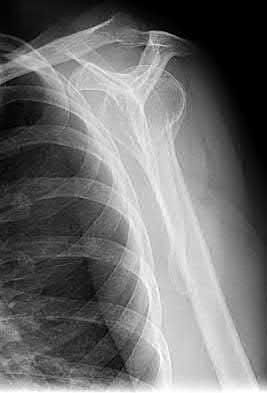

2. # A 35-year-old woman is involved in a head-on collision while driving. Initial radiographs are shown in Figures 8a and 8b. Injury to what vessel increases the risk for osteonecrosis of the injured bone?

5. Artery of the tarsal sinus Corrent answer: 4

The patient has a Hawkins type III talar neck fracture-dislocation with a risk of osteonecrosis ranging from 69% to 100%. Anatomic studies have shown that the artery of the tarsal canal supplies the lateral two thirds of the talar body.

The other vessels listed provide no significant contribution to the talus.